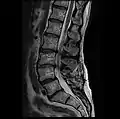

For spinal stenosis

Most commonly, a laminectomy is performed to treat spinal stenosis. Spinal stenosis is the single most common diagnosis that leads to spinal surgery, of which a laminectomy represents one component. The lamina of the vertebra is removed or trimmed to widen the spinal canal and create more space for the spinal nerves and thecal sac. Surgical treatment that includes a laminectomy is the most effective remedy for severe spinal stenosis; however, most cases of spinal stenosis are not severe enough to require surgery. When the disabling symptoms of spinal stenosis are primarily neurogenic claudication and the laminectomy is done without spinal fusion, there is generally a more rapid recovery with less blood loss.[3] However, if the spinal column is unstable and fusion is required, the recovery period can last from several months to more than a year, and the likelihood of symptom relief is far less probable.[4]

In most known cases of lumbar and thoracic laminectomies,[5] patients tend to recover slowly, with recurring pain or spinal stenosis persisting for up to 18 months after the procedure. According to a World Health Organization census in 2001, most patients who had undergone a lumbar laminectomy recovered normal function within one year of their operation.

Back surgery can relieve pressure on the spine, but it is not a cure-all for spinal stenosis. There may be considerable pain immediately after the operation, and pain may persist on a longer-term basis. For some people, recovery can take weeks or months and may require long-term occupational and physical therapy. Surgery does not stop the degenerative process and symptoms may reappear within several years.[1]